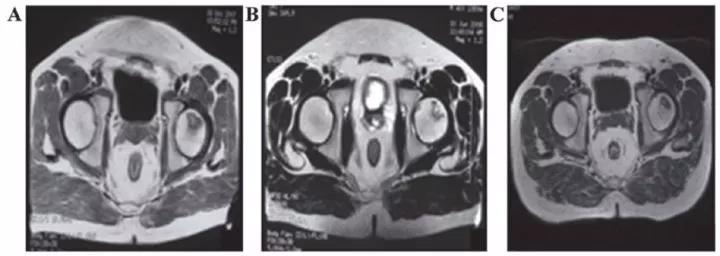

? 勃起功能障礙

運(yùn)用干細(xì)胞治療勃起功能障礙一方面可以完全取代受損和死亡的陰莖組織細(xì)胞,另一方面可以分泌一些因子修復(fù)功能受損的陰莖組織細(xì)胞。

丹麥15位勃起功能障礙患者在未接受藥物或陰莖移植術(shù)的情況下接受間充質(zhì)干細(xì)胞的輸注,6個(gè)月后,8名男性能夠正常性交。